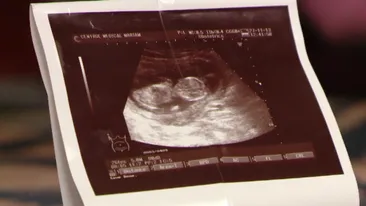

Un medic i-a făcut, din greșeală, avort unei gravide. Cum a fost posibil așa ceva

O gravidă din Timişoara a mers la ginecolog să facă avort, însă după câteva zile a constat că era tot însărcinată! Ce a urmat e copleşitor: „E posibil sa fi scos doar…”